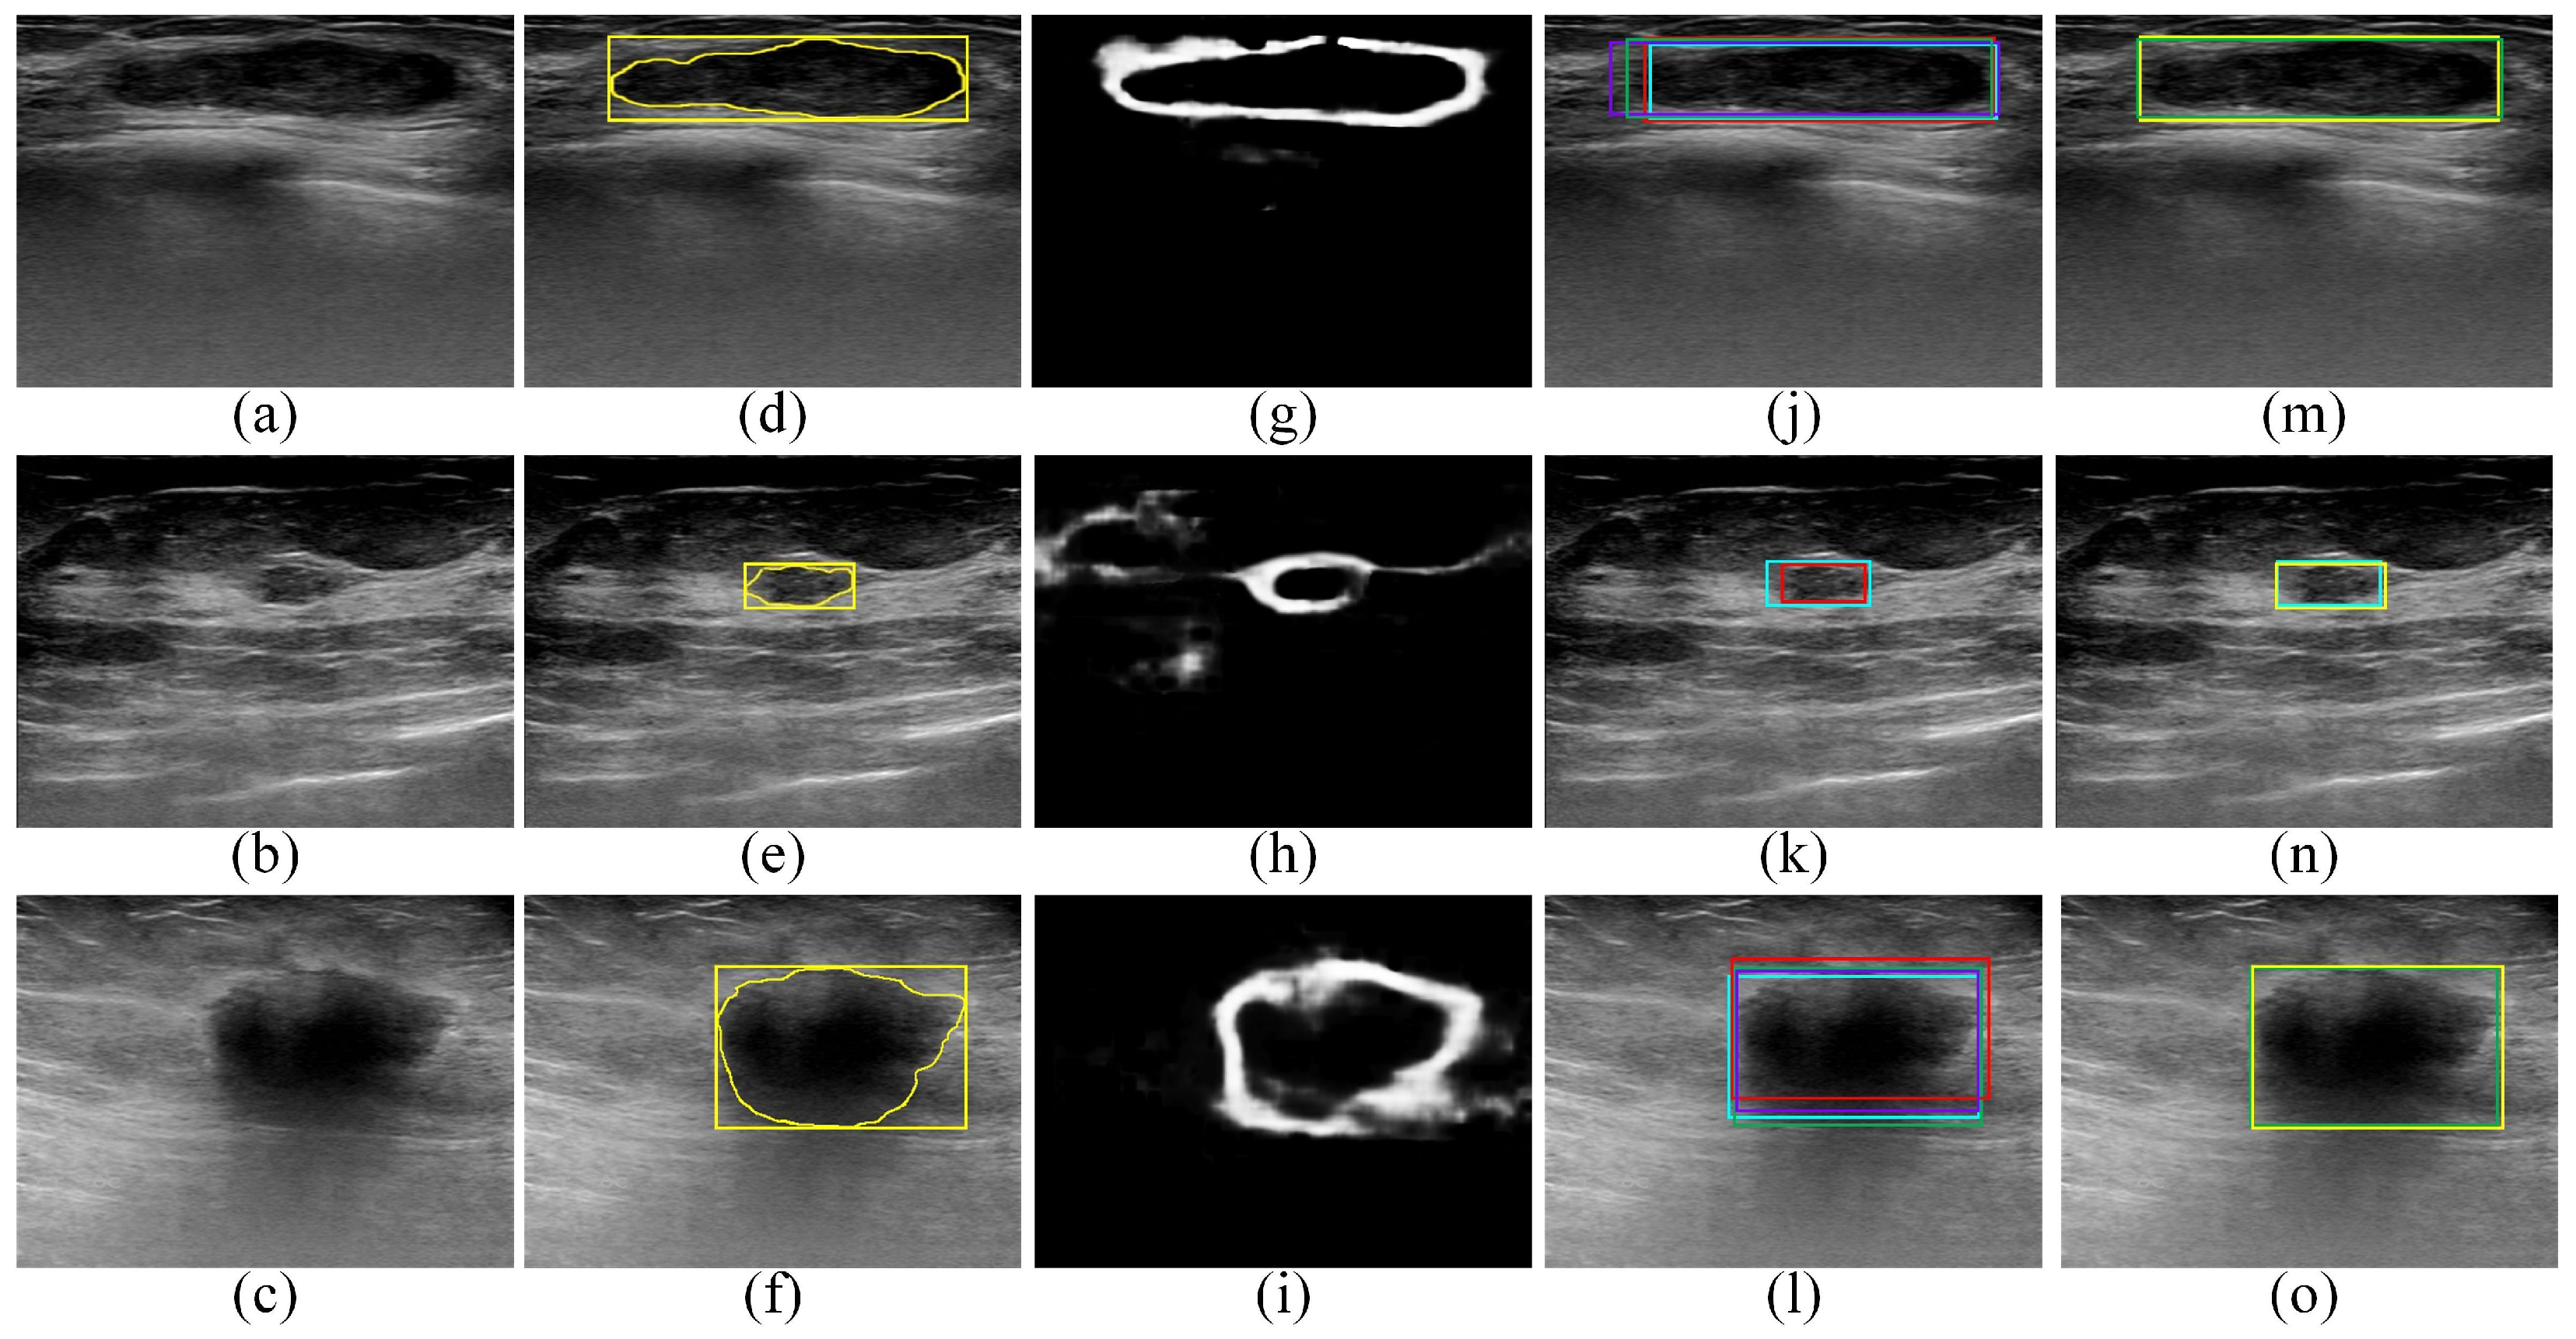

Figure 5 provides qualitative ROI localization results obtained for the UJH dataset by the Faster R-CNN, SSD, EfficientDet-D0, and CenterNet object-detection models as well as the proposed edge-based selection method. The qualitative results provided in Figure 5 demonstrate that the proposed edge-based selection method was able to process the ROIs generated by the four deep learning object-detection models to select the ROI that improves the localization of the region that contains the tumor.

Figure 5.

Qualitative results obtained for the UJH dataset. (a–c) BUS images acquired for (a) benign tumor and (b,c) malignant tumors. (d–f) The gold standard tumor outlines (yellow outlines) and the gold standard ROIs (yellow boxes) overlaid on the BUS images. (g–i) The edge maps computed using the DexiNed model. (j–l) The ROI localizations generated by the Faster R-CNN (violet boxes), SSD (red boxes), EfficientDet-D0 (cyan boxes), and CenterNet (green boxes) models overlaid on the BUS images. In (k), the Faster R-CNN and CenterNet models failed to generate ROIs. (m–o) The ROIs selected by the proposed edge-based selection method as well as the gold standard ROIs (yellow boxes) overlaid on the BUS images. In (m–o) the proposed edge-based selection method selected the ROIs generated by the CenterNet, EfficientDet-D0, and CenterNet models, respectively.